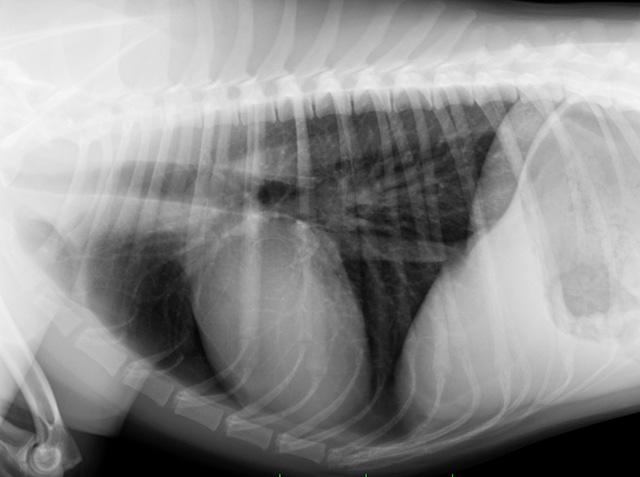

不妊・去勢手術の実績も豊富にあり(以前の病院で年間100件ほど)、早く的確な手術で動物の負担を減らします。また皮内縫合という表面に糸を出さない縫い方や、マイクロ波メスを使って血管を処理するので糸を使わず早く・安全に手術を行うことができます。このように、動物の負担を減らす工夫をいくつも行っています。

当院では麻酔管理に力を入れています。麻酔や循環器への豊富な知識を用い、また人工換気機や麻酔モニター、点滴装置など医療機器を適切に使い、安全で安心な麻酔を行います。幸いなことに健康な子の麻酔で、重篤な合併症や死亡事故が起こったことはありません。今後もさらに麻酔に力を入れていき、安全な麻酔を行い続けます。